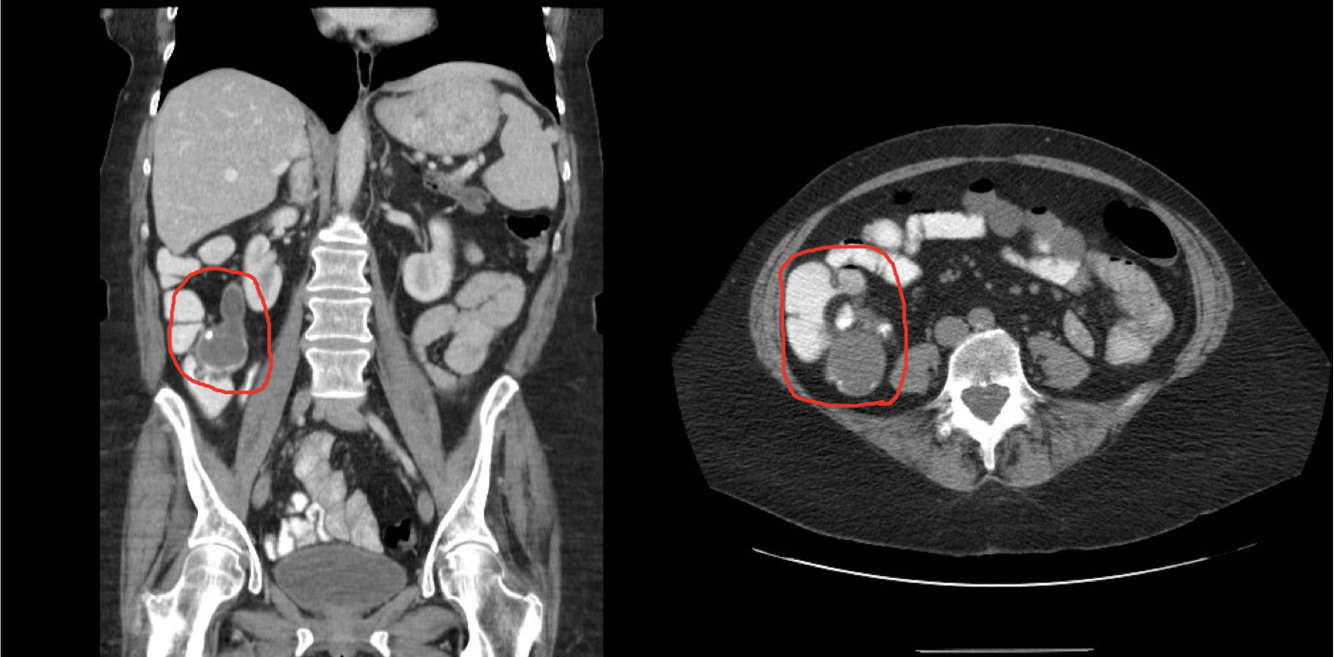

What is circled? What is the line pointing at?

Circled- R ovary w/ aggressive tumor

Line - Normal L ovary